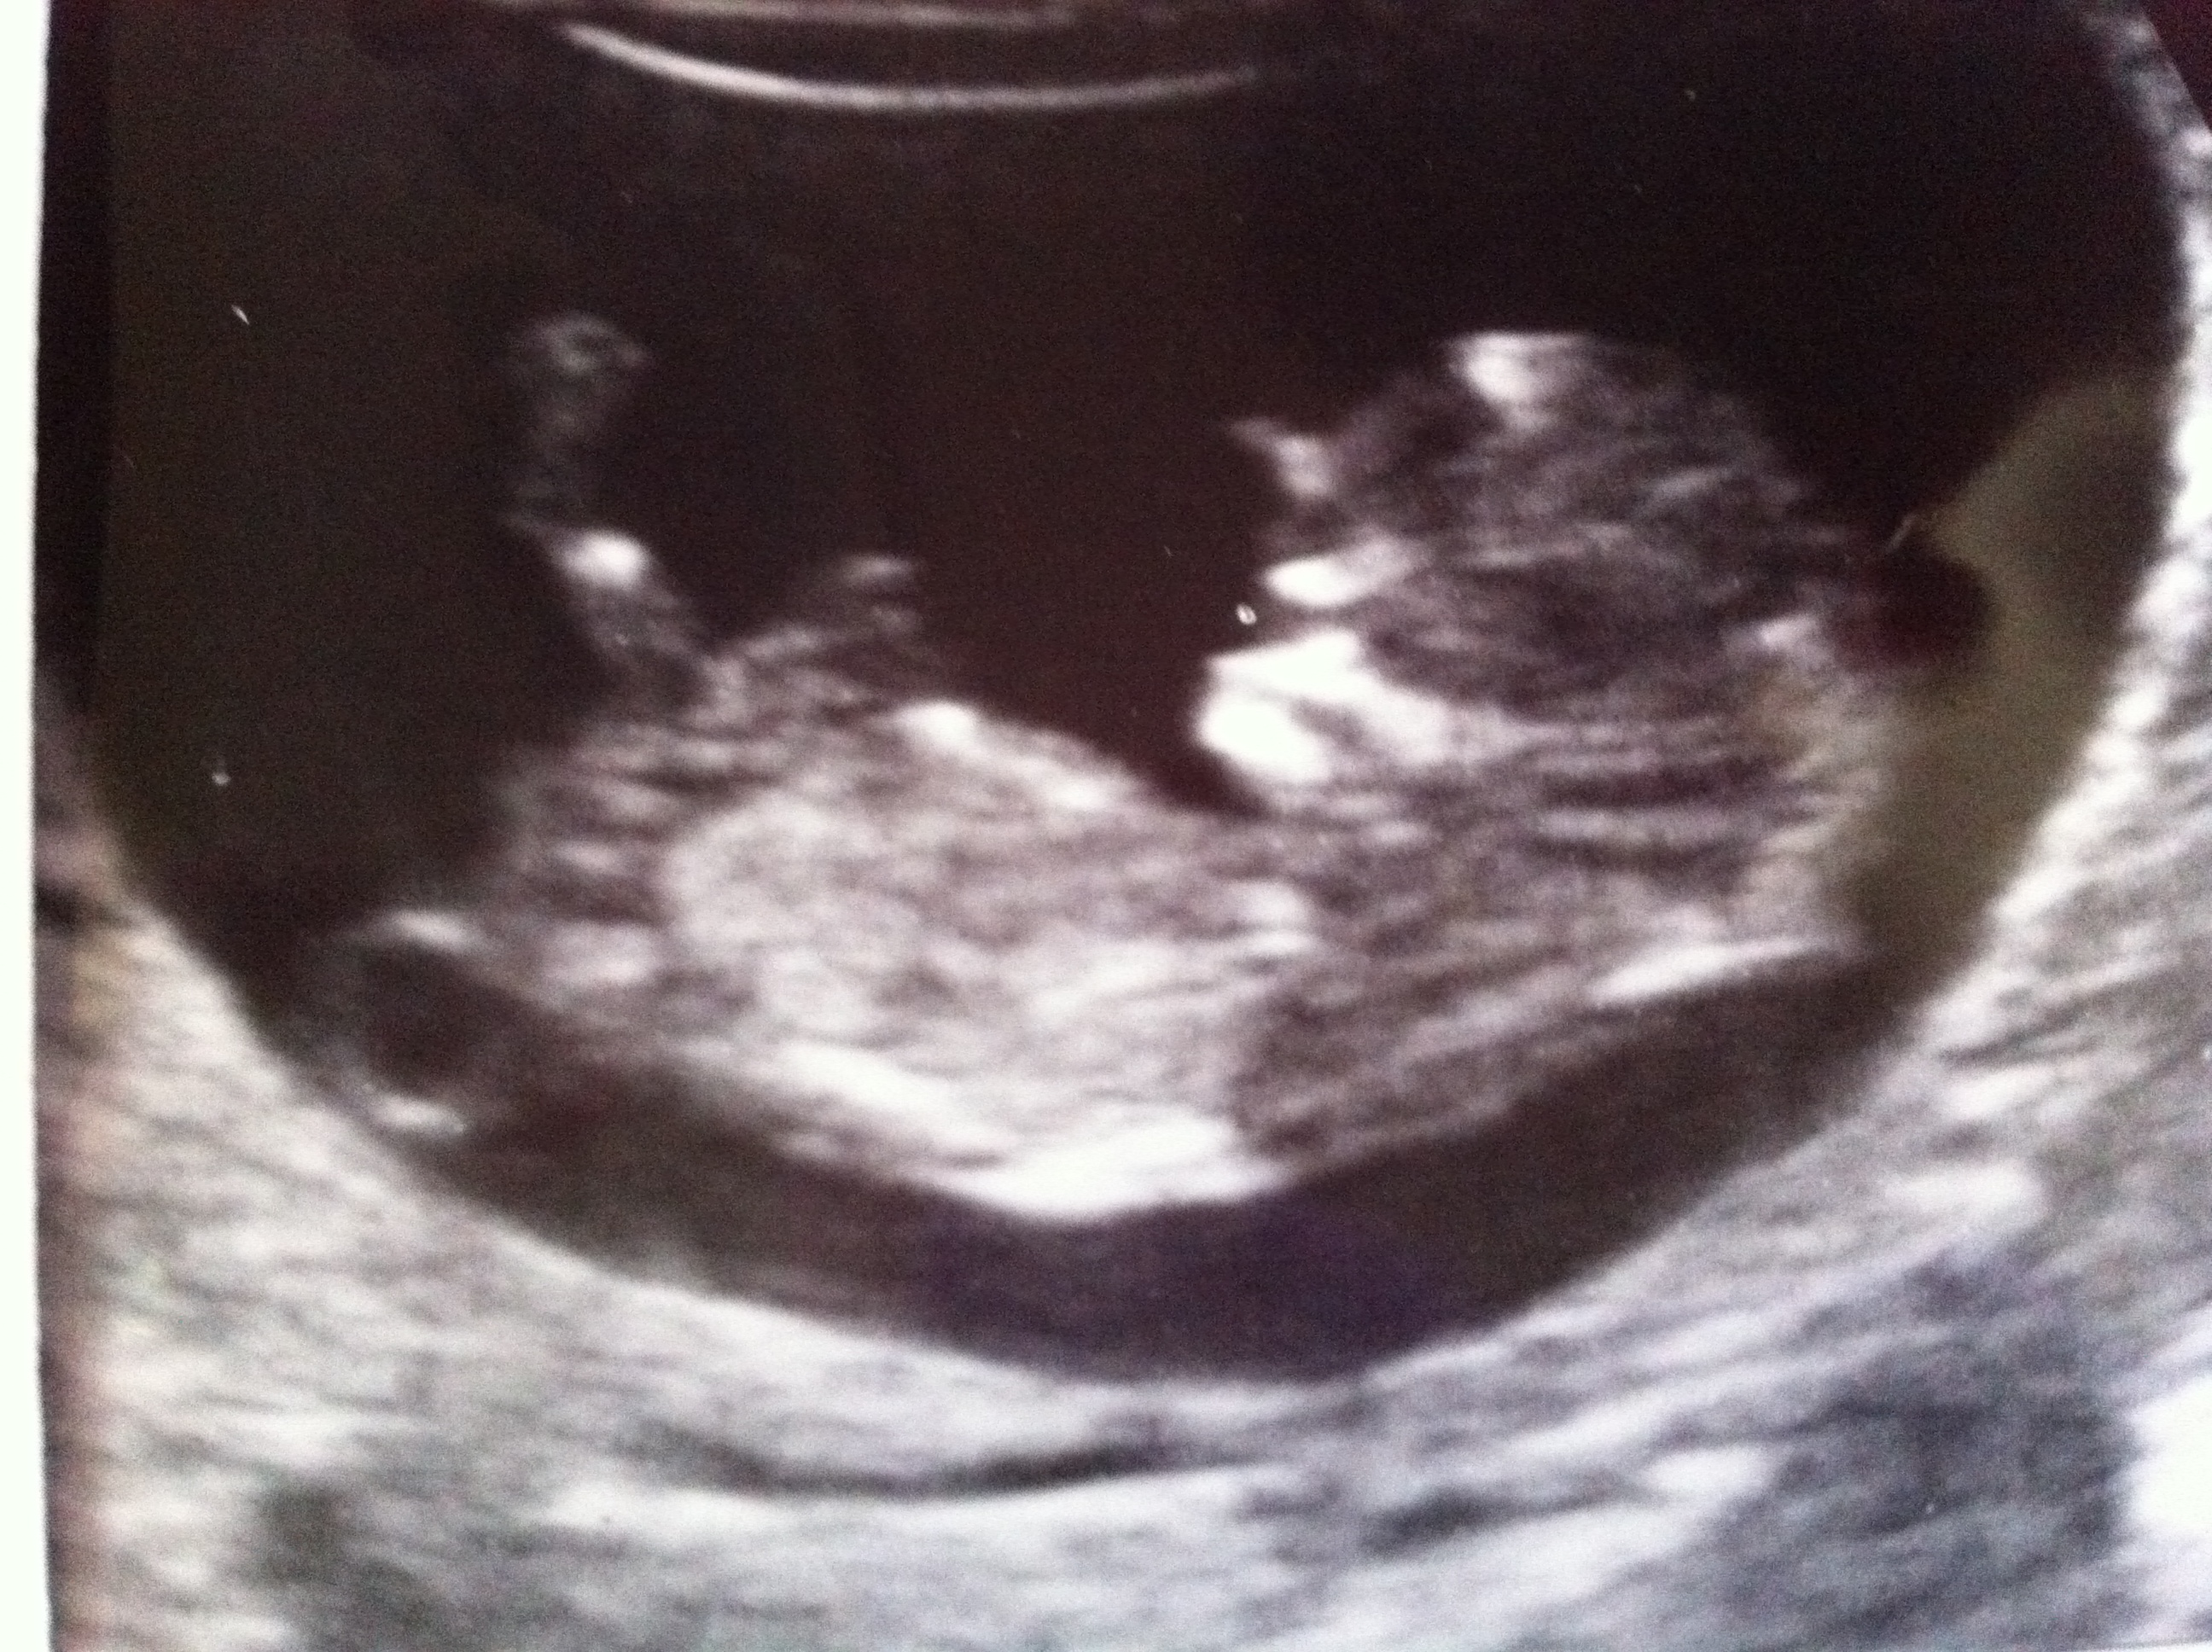

Hi last minute guesses on nub please anyone we hope for a little girl as we already have 4 boys,but we happy slong as he or she is healthy so any guesses are greatly appreciated thanks

What gestation is this pic? x

11 weeks and 4 days thank

I am leaning girl for you... but can't be toooo sure wish I could be though!!!! Do you have any more pics???

Tricky nub!